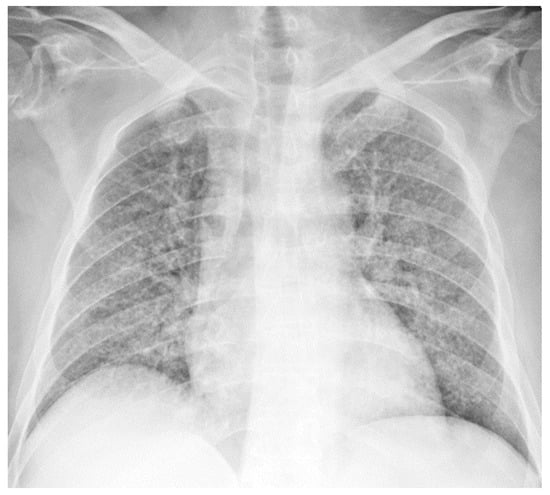

2.3. Chest Radiograph